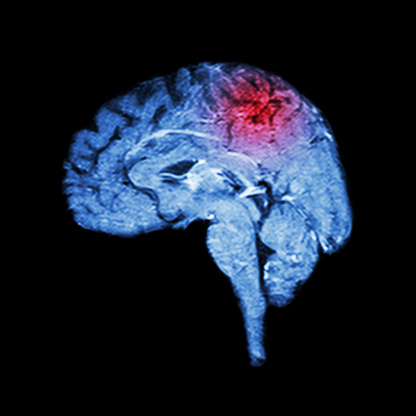

Lacunar infarct is a type of stroke that occurs when one of the arteries supplying blood to the brain gets blocked. These arteries are quite small, which makes them vulnerable to damage. While most arteries in the body gradually become smaller, the arteries of the lacunar stroke branch off a large high-pressure artery. Lacunar stroke ...click here to read more